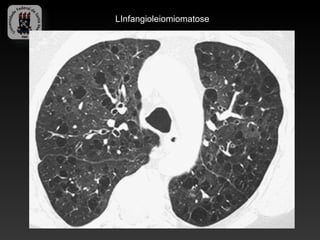

-LINFANGIOLEIMIOMATOSE

-Doença rara de etiologia incerta, caracterizada pela proliferação

desordenada de células musculares lisas.

-Afeta exclusivamente mulheres em idade reprodutiva.

-Achados:

-Finas apacidades reticulonodulares bilaterais (precoce)

-Hiperinsuflasão, faveolamento, reticulados grosseiros, derrames pleurais

quilosos e pneumotorax.

-TC: incontáveis cistos, com paredes finas e espalhados uniformemente.

-Parenquima pulmonar relativamente normal.

LInfangioleiomiomatose